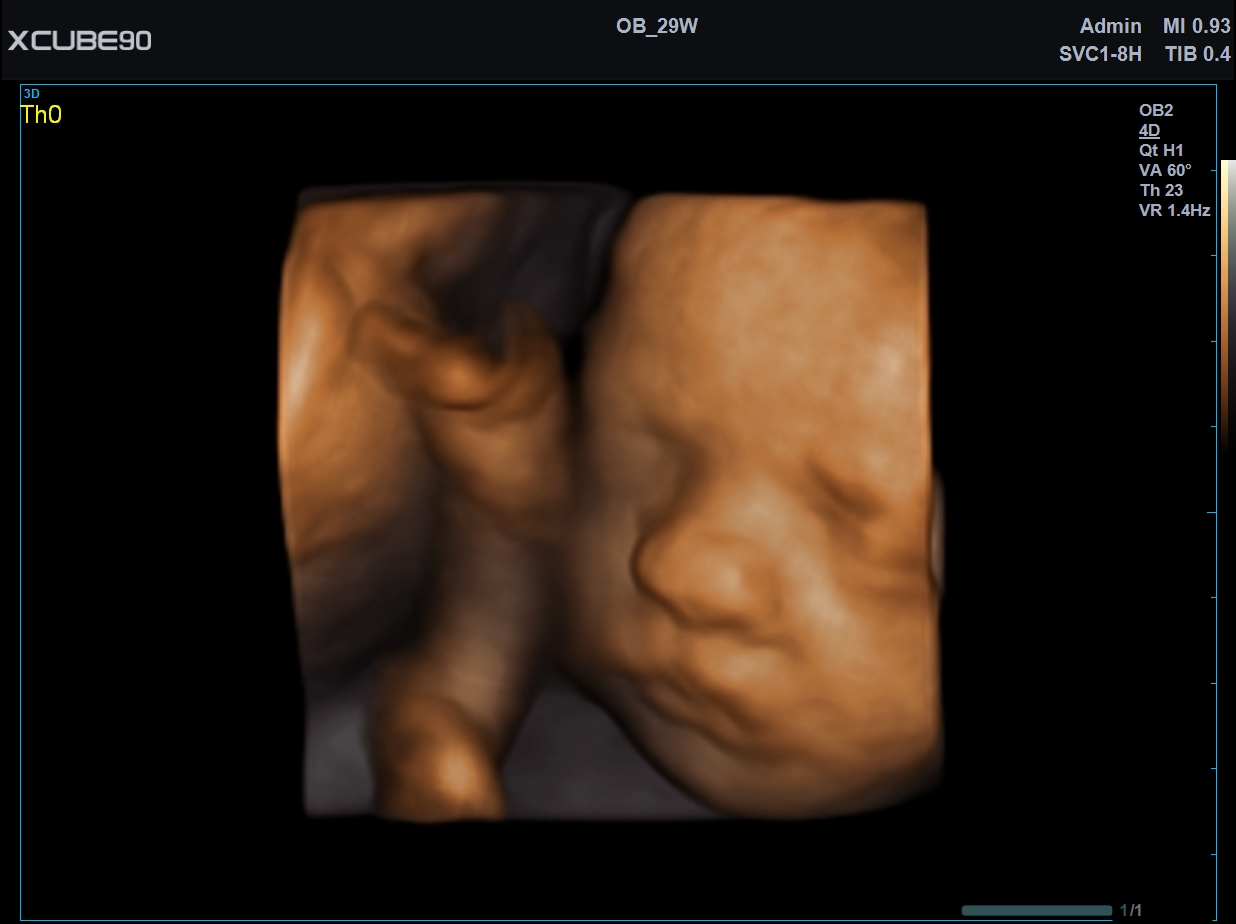

| Software Disponibles OB/GIN: | 3D/4D convexo y endocavitario, Live HQ, Volume Advance, Auto Translucencia Nucal (NT), X+ Auto Biometry, X+ Auto Follicle, Silhouette View, Volume SRI |

| Transductores: | Lineal 3~19MHz (256 cristales), Lineal 10~25MHz, Convexo 1~7MHz, Endocavitario 2~11MHz, Convexo Volumétrico 1~8MHz, Endocavitario Volumétrico 3~10MHz, Phased Array (alta resolución), TEE |